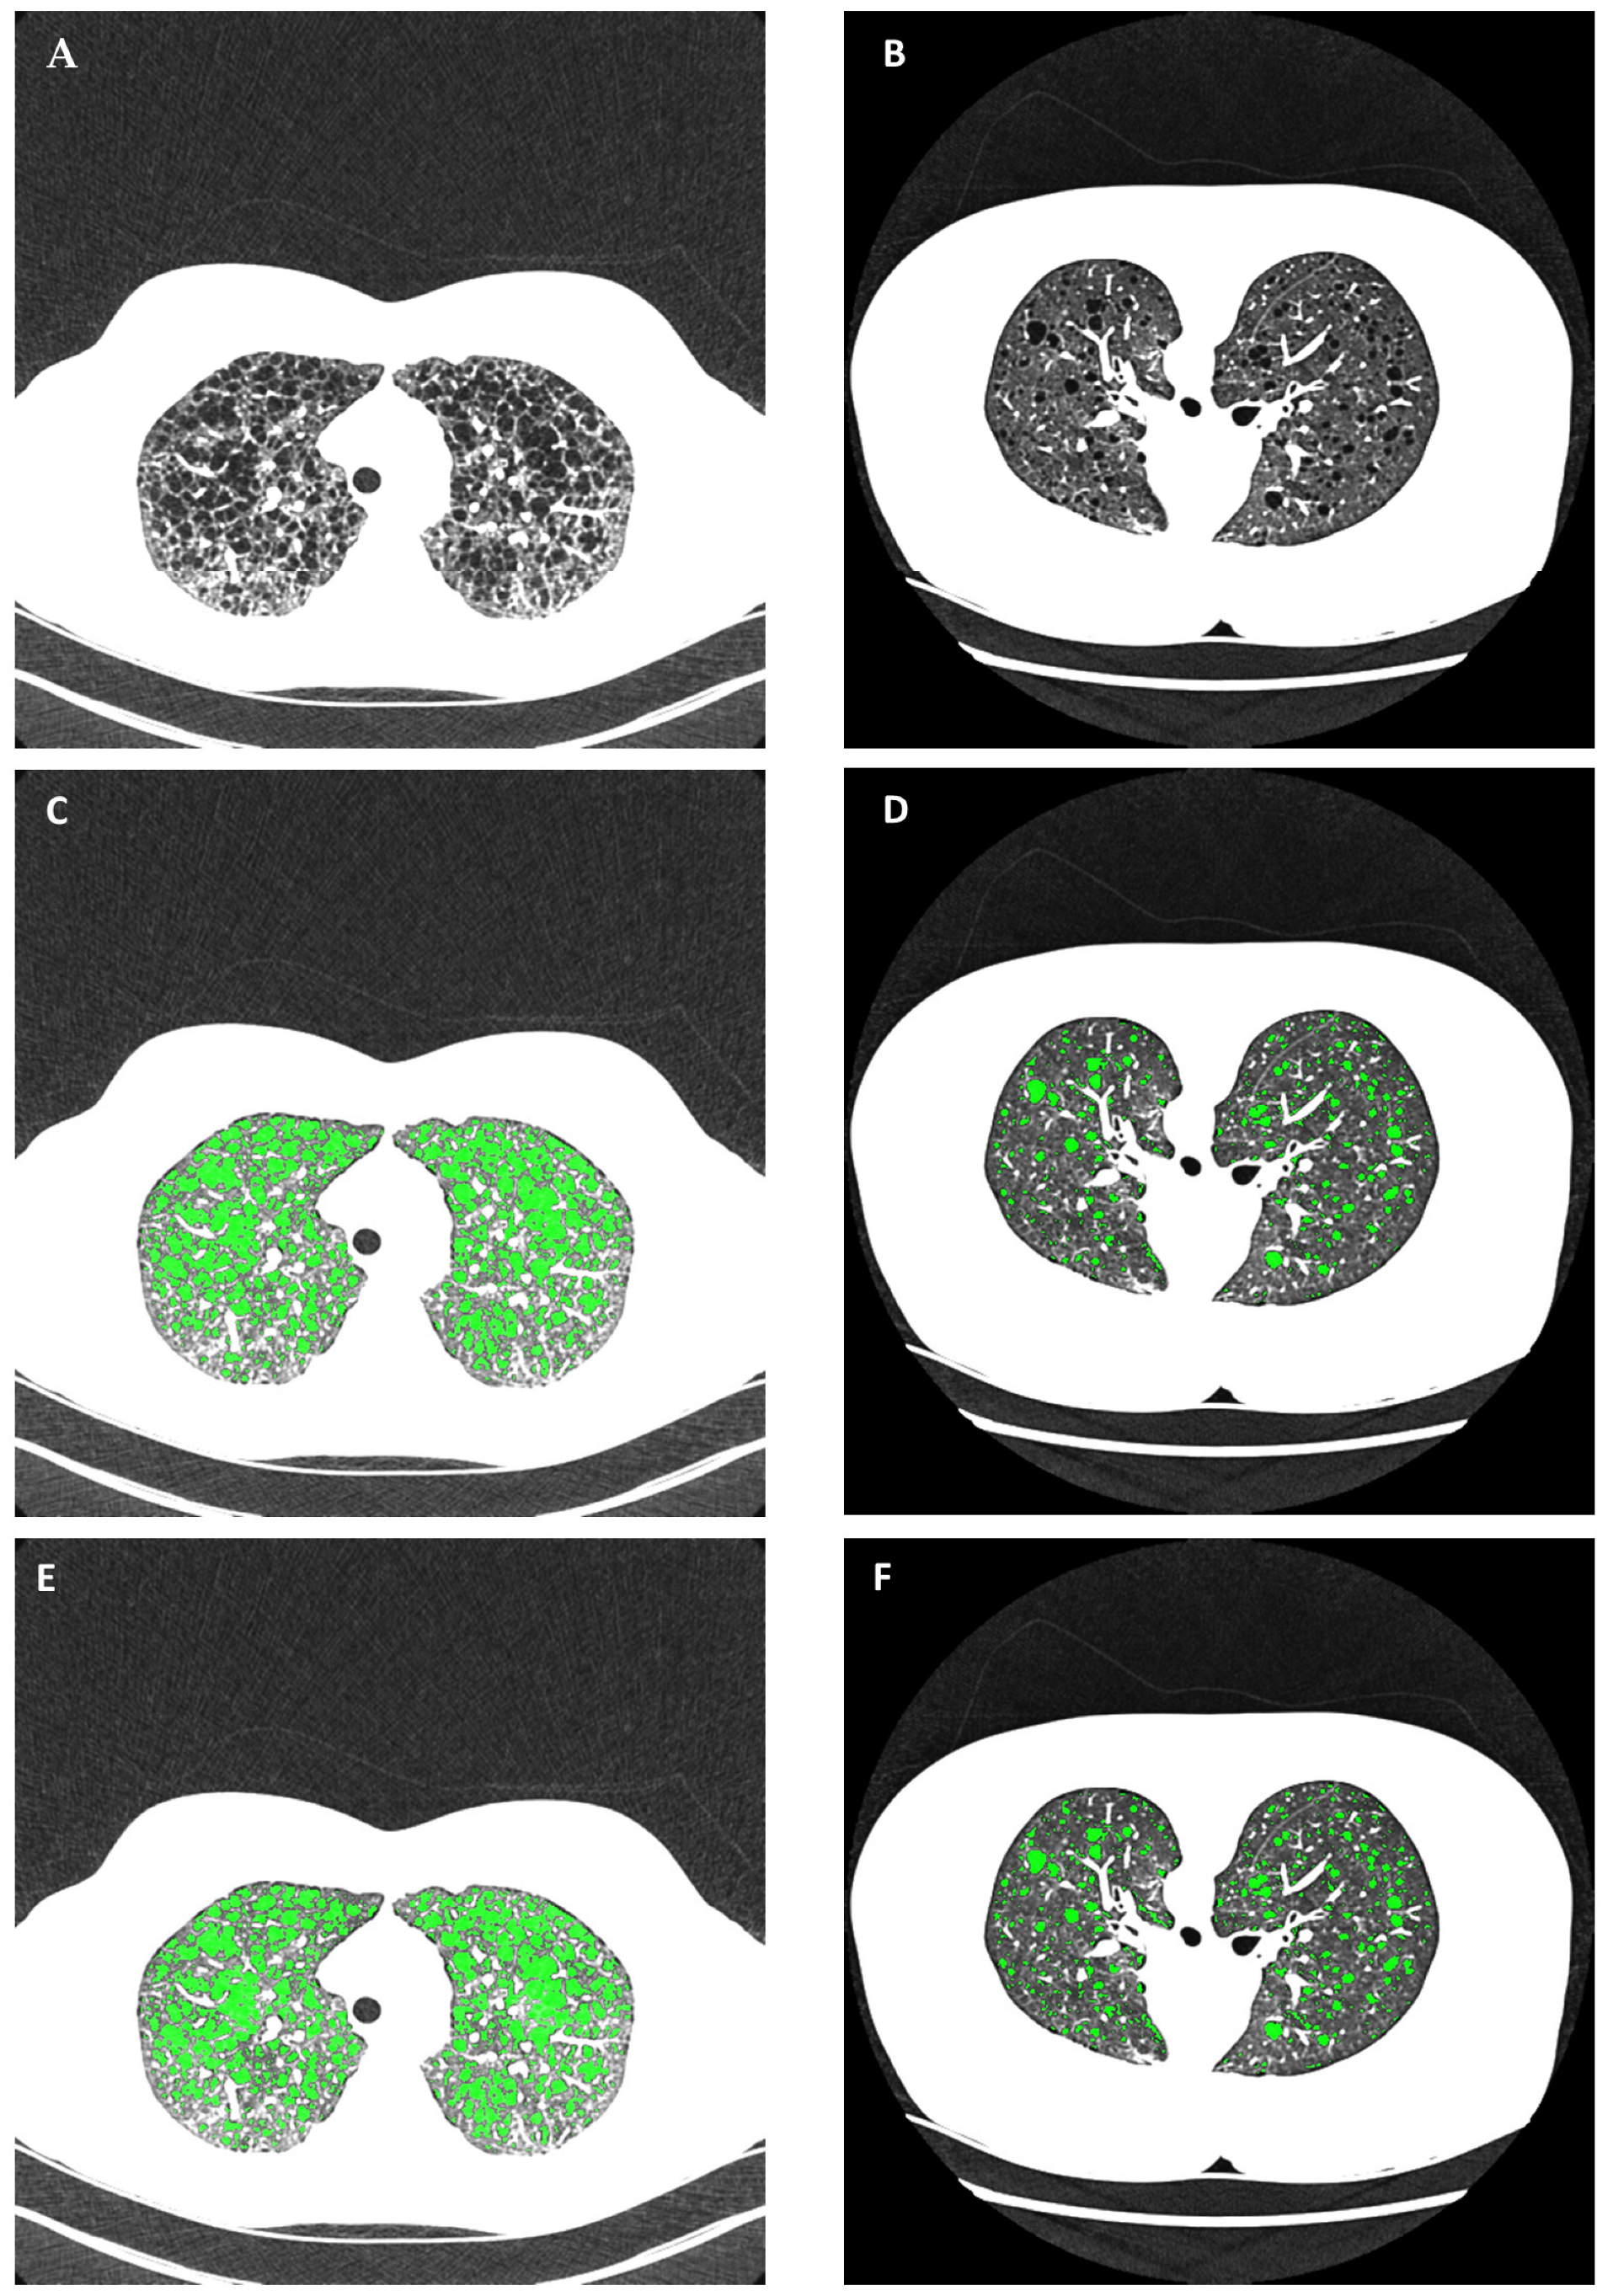

Figure 4.

An example of the variability in the radiodensity of air and non-cystic lung parenchyma across different patients and scanner platforms and the consequences on cyst segmentation. (A,B) Chest HRCT scans of two patients from two different scanner platforms in supine and prone positions, respectively. Both are displayed in the grayscale range of −1050 HU to −600 HU to highlight lung parenchymal structures. The average radiodensity of the air background outside the body was −971 HU in (A) and −1006 HU in (B). The average radiodensity of non-cystic lung parenchyma was −805 HU in (A) and −918 HU in (B). (C,D) Optimal cyst segmentation was determined by a trained operator using the gold-standard commercial semi-automated software. The threshold radiodensity for cystic areas was adjusted by the operator to −880 HU for the image series in (A) and −970 HU for the image series in (B). The cystic areas are highlighted in green. (E,F) Automated cyst segmentation without user input. The automated method accounted for the variability of radiodensity values to provide the appropriate segmentation (highlighted in green).

In all statistical results, a p-value of less than 0.05 is considered statistically significant. An example comparing automated cyst segmentation with commercial semi-automated segmentation is given in Figure 4. The example included two image series from two patients with markedly different radiodensities of the lung parenchyma (Figure 4A,B). In the gold-standard semi-automated analysis, the operator set the global threshold for cysts to −880 HU and −970 HU, respectively, to attain satisfactory segmentation in each series (Figure 4C,D). The automated method provided appropriate cyst segmentation in both series without user input (Figure 4E,F).